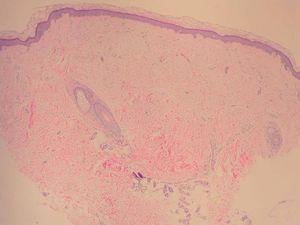

Una mujer de 52 años, sin antecedentes patológicos de interés, acudió a la consulta de dermatología de nuestro hospital por presentar lesiones cutáneas asintomáticas en el dorso de las manos desde hacía 4 años. Según la paciente, el proceso se había iniciado en el dorso de la mano derecha y había progresado lentamente hasta estabilizarse unos dos años después. En la exploración física se apreciaban lesiones papulosas firmes de tono blanquecino en el dorso de ambas manos y, de manera muy aislada, en la zona dorsal de las muñecas (fig. 1). Se realizó una biopsia cutánea de una de las lesiones, observándose una epidermis ligeramente atrófica y una llamativa separación de los tractos conectivos dérmicos por depósito de un material azul alcián positivo que correspondía a mucina (figs. 2 y 3). Se reconocía, además, una ligera rotura de fibras elásticas con técnica de orceína. El resultado de la biopsia fue histológicamente compatible con mucinosis cutánea. Todas las exploraciones analíticas fueron normales, incluyendo hemograma, pruebas de función hepática, renal y tiroidea, inmunoglobulinas en sangre y proteinograma. Hasta el momento, las lesiones permanecen estables.

Fig. 2.--Pápula con ligera separación de las fibras colágenas dérmicas. (Hematoxilina-eosina, x 4.)